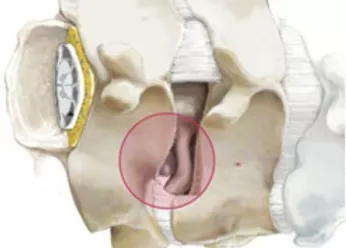

Схематическое изображение фораминтомии и корешка, то места вскрытия позвоночного канала, чтобы удалить грыжи. Размер такого окна всего несколько миллиметров. На втором фото показана работа инструментом во время удаления грыжи.